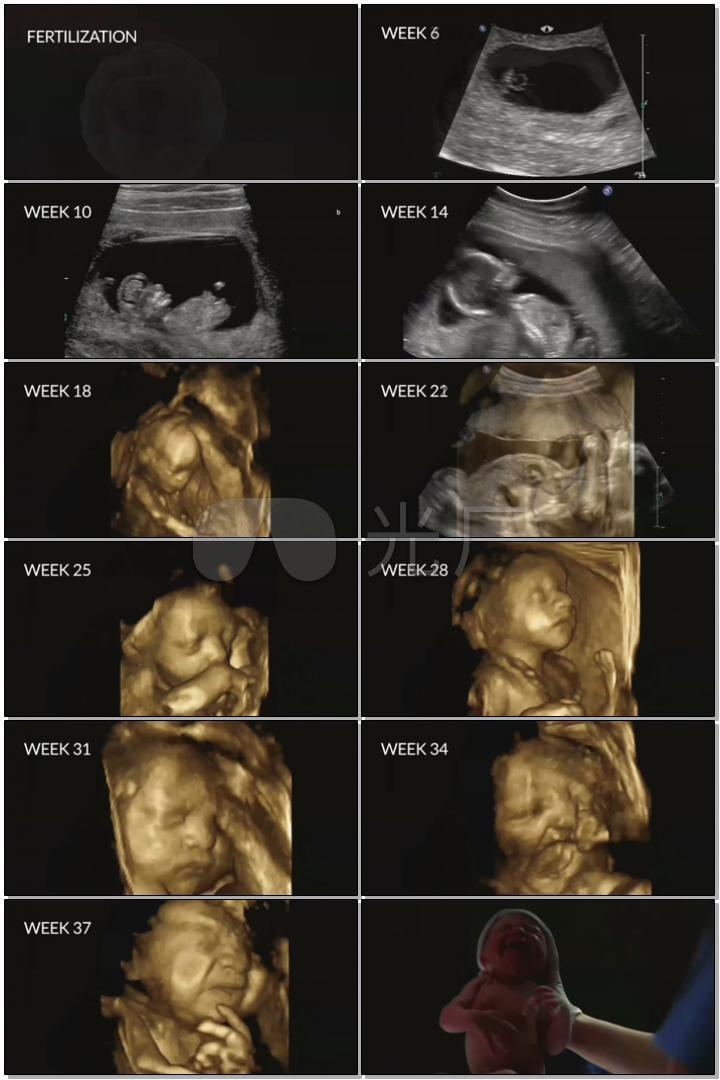

子宫受精怀孕胎儿发育出生(全程影像)

怀孕1-40周完整详细的胎儿发育过程图(彩色3d图)

怀孕1-42周的3d胎儿超声图,好神奇!